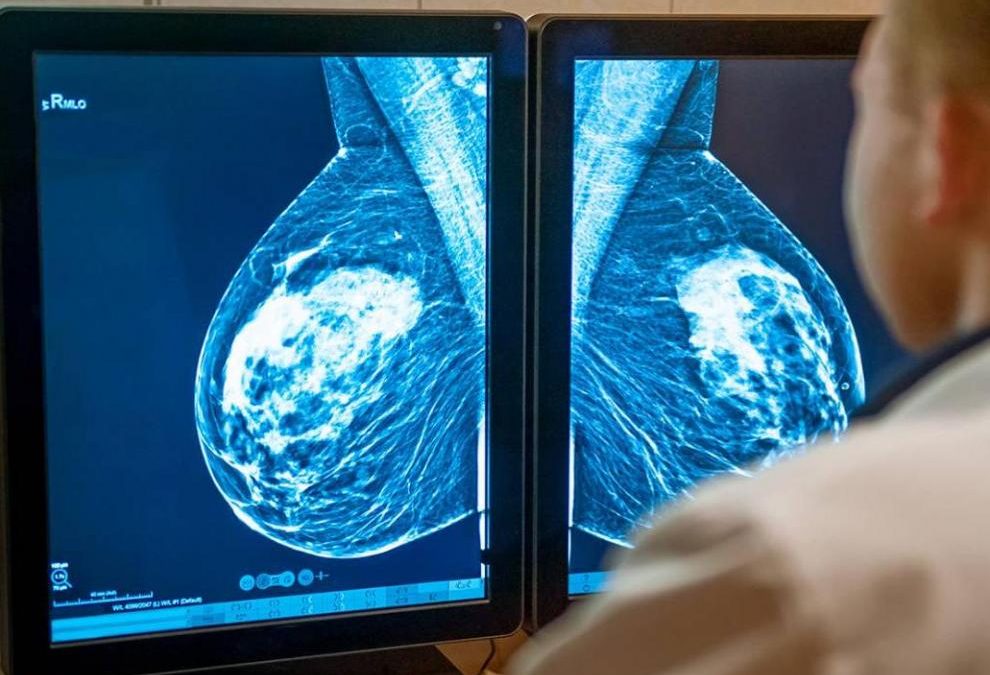

Un fármaco que actúa como un "caballo de Troya", engañando a las células cancerígenas para entrar en ellas y atacarlas, se ha demostrado eficaz para frenar la progresión de un cáncer de mama agresivo -HER2 positivo con metástasis- e incluso es capaz de eliminar el tumor en el 16 % de los casos.

En concreto, el ensayo de fase III DESTINY-Breast 03 ha evaluado la eficacia del Trastuzumab deruxtecan en pacientes con cáncer de mama HER2 positivo con metástasis y que ya habían recibido tratamientos con anterioridad.